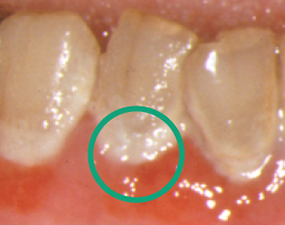

プラークは歯を磨かないでいるとやがて表面がザラザラ、べたべたしてきます。

よく見ると黄色の粘着物が...。

それこそがプラーク(バイオフィルム)です。